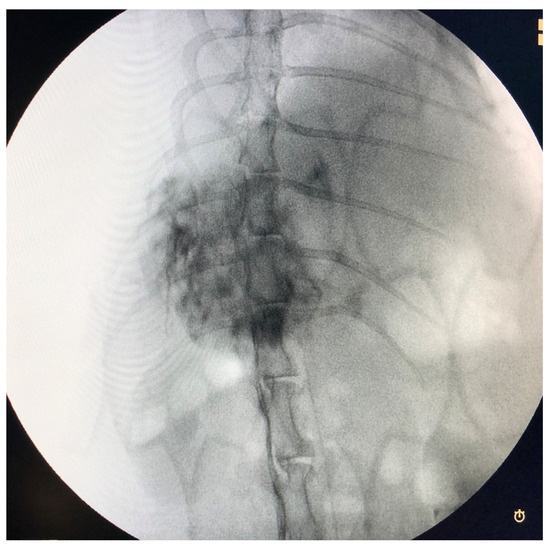

2.3. Trans-Arterial Chemoembolization (TACE) Procedure